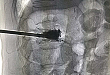

近日,济南市第三人民医院脊柱外科成功为一名骨质疏松症导致腰椎骨折的 9 旬患者实施了「经皮椎体后凸成形术」。手术只用了半小时,除了腰部一个 4 mm 的创口,其...

脊柱外科根据颈肩腰腿痛患者具体情况选择个体化治疗治疗方案,坚持「安全、微创、经济、快捷」的原则,充分体现以人为本的诊治理念,使患者满意,让家属放心。患者第一...